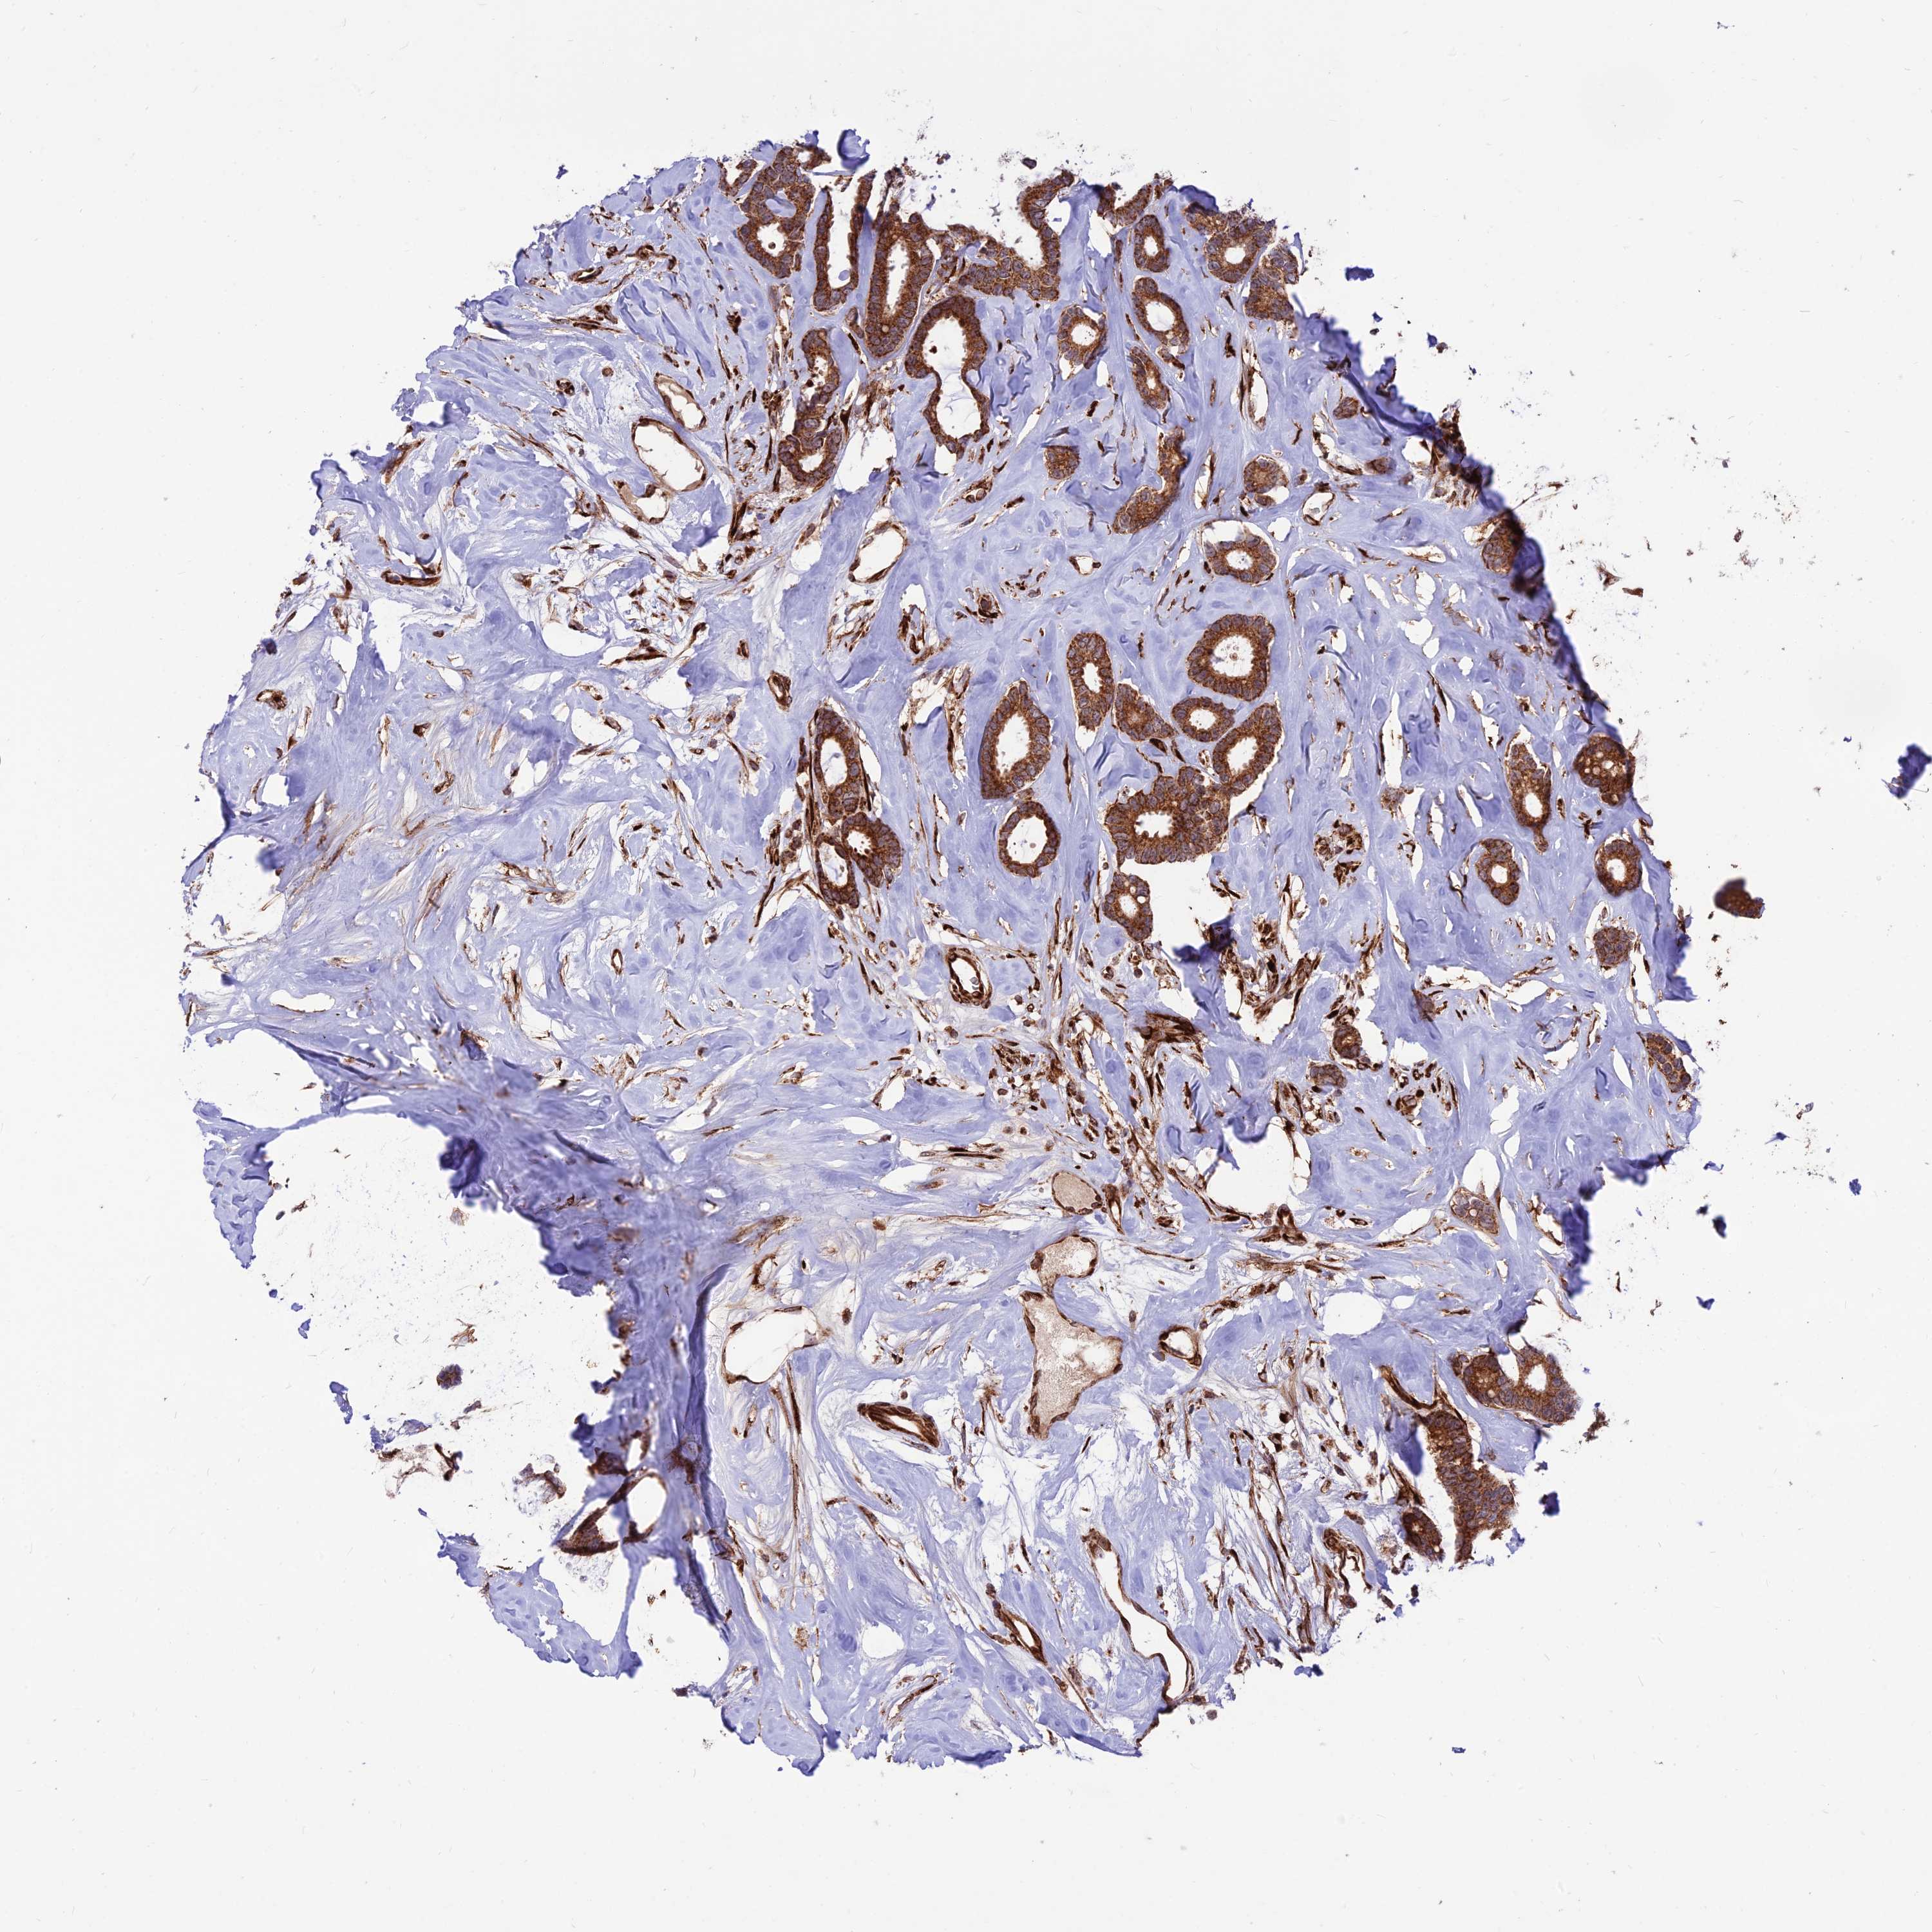

CANCER BREAST CANCER Show tissue menu

BRCA TCGA BRCA VALIDATION PROTEIN EXPRESSION